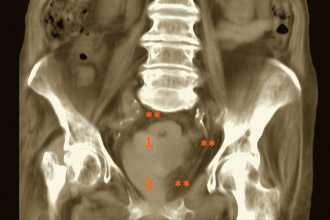

Трансабдоминальное ультразвуковое исследование

Несколько уступает в качестве ТРУЗИ, осуществляется доступом через переднюю брюшную стенку. Не рекомендовано для выполнения у мужчин с ожирением.